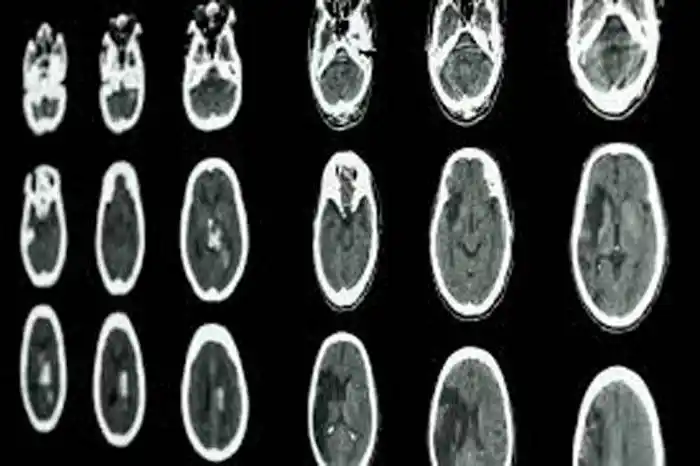

Los ACV son siempre una emergencia aún en tiempos de pandemia. Ocurren cuando se interrumpe el flujo de sangre hacia el cerebro y sin oxígeno las neuronas comienzan a morir, reduciendo la función cerebral. Existen diversas clases de ACV: el ACV Isquémico (85% de los casos, un coágulo o trombo obstruye un vaso sanguíneo del cerebro), el ACV isquémico transitorio, en el cual los síntomas se recuperan rápidamente y el ACV Hemorrágico (15%, por rotura de una arteria cerebral).